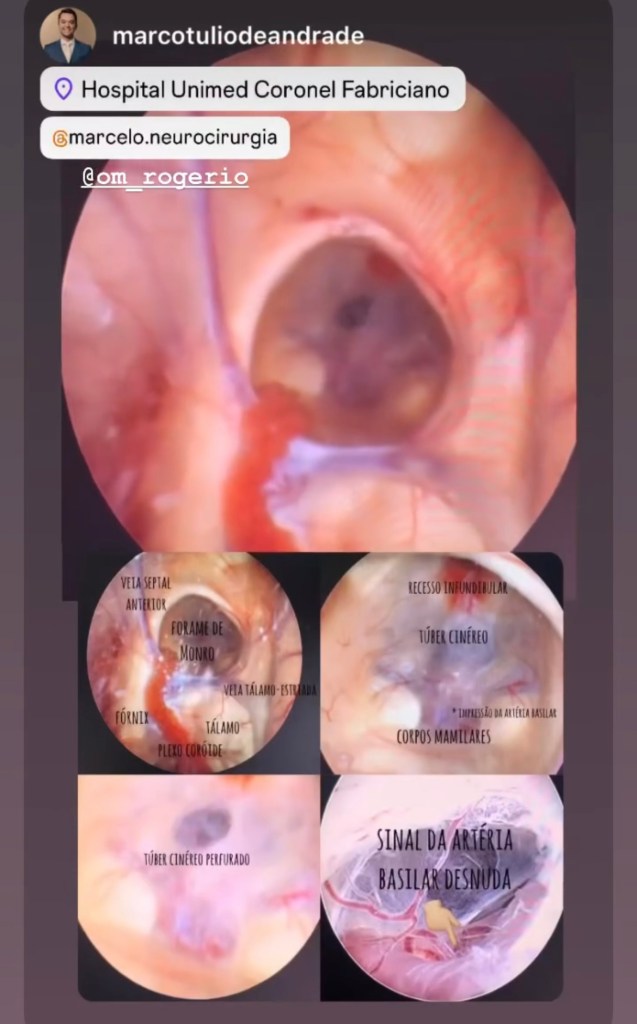

GALERIA De cirurgias

Abaixo você pode conferir imagens de algumas cirurgias já realizadas por Dr. Marcelo Camargos. Caso tenha alguma dúvida ou interesse, não deixe de fazer contato para maiores esclarecimentos!